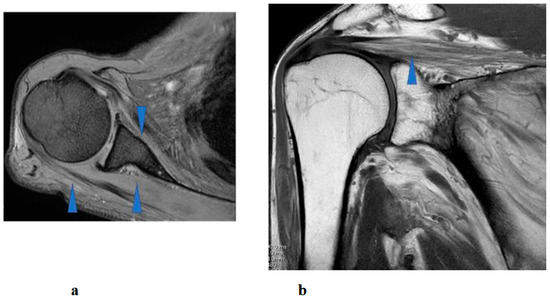

Hybrid Assistive Limb Treatment for the Shoulder and Elbow Joints Enabled Recovery from Chronic-Phase Severe C5 Palsy Following Cervical Spine Surgery

J. Clin. Med. 2025, 14(21), 7520; https://doi.org/10.3390/jcm14217520 - 23 Oct 2025

Postoperative C5 palsy is a common complication of cervical spine surgery. Inadequate recovery from C5 palsy can result in significant impairment of activities of daily living. However, no effective treatment has been established for persistent cases. In the present report, we describe a [...] Read more.

Postoperative C5 palsy is a common complication of cervical spine surgery. Inadequate recovery from C5 palsy can result in significant impairment of activities of daily living. However, no effective treatment has been established for persistent cases. In the present report, we describe a novel therapeutic approach using the Hybrid Assistive Limb (HAL) in a patient with severe, prolonged postoperative C5 palsy. The patient was a 46-year-old man who developed severe right C5 palsy following cervical spine surgery performed 41 months earlier. Despite undergoing conventional rehabilitation, no improvement was observed, and the muscle strength of the right deltoid and biceps remained at manual muscle testing (MMT) grade 2. HAL training, using both shoulder and elbow devices, was initiated at our institution. Training was conducted once weekly for a total of 106 sessions over 21 months. At baseline, the right shoulder range of motion was limited to 50° in flexion and 35° in abduction. With HAL-assisted training, flexion improved to 150° and abduction improved to 95° by the final (106th) session and further increased to 165° and 170°, respectively, at long-term follow-up. Deltoid strength, assessed using handheld dynamometry, increased from 3.5 Nm/kg at baseline to 28.5 Nm/kg after training. In this case, a long-term therapeutic program incorporating shoulder and elbow HAL training successfully improved severe and prolonged postoperative C5 palsy to a functionally useful level. This case highlights the potential effectiveness of HAL therapy for treatment-resistant postoperative C5 palsy. Full article